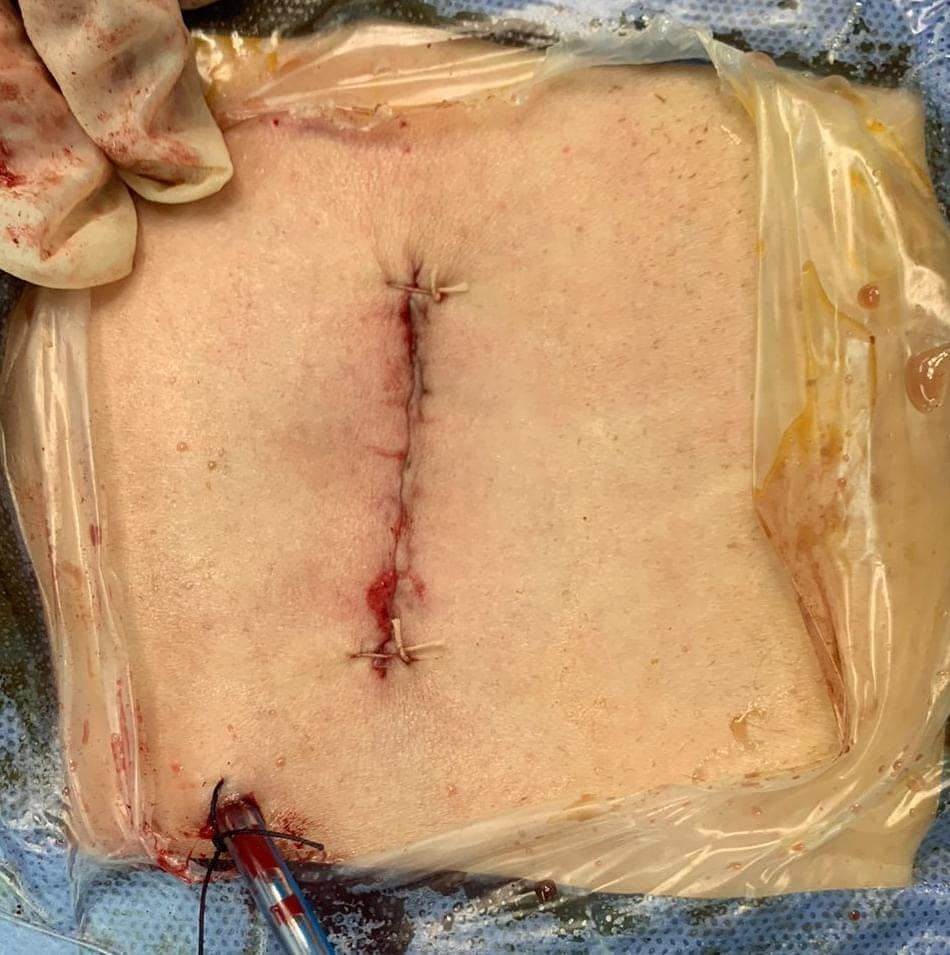

وقال الدكتور تامر حمدى أحمد مدير عام مستشفى بئر العبد التخصصى (في بيان) أنه تحت رعاية الدكتور خالد عبدالغفار وزير الصحة والدكتورة مها إبراهيم رئيس أمانة المراكز الطبية المتخصصة، والدكتور خالد الدرندلى رئيس جامعة الزقازيق والدكتور أحمد عنانى عميد كلية طب الزقازيق والدكتور محمود مصطفى طه رئيس قسم جراحة المخ والأعصاب بجامعة الزقازيق.. حيث قام الدكتور محمود محمد متولى مدرس مساعد جراحة المخ والأعصاب بجامعة الزقازيق بمساعدة الدكتور محمود الوكيل مدرس التخدير بالقصر العينى جامعة القاهرة باجراء جراحة لمريضة عمرها ٤٠عاما كانت تعانى من آلام شديدة وعرق نسا بالساق اليسرى تمنعها من المشى وممارسة حياتها اليومية بشكل طبيعى، وكانت لا تستجيب للعلاج، وأظهر الرنين المغناطيسى وجود انزلاق غضروفى ما بين الفقرات الخامسة القطنية والعجزية الأولى واختناق بجذور أعصاب الساق اليسرى، وقد تم تجهيز المريض ودخول العمليات واجراء جراحة لاستئصال الغضروف وتسليك جذور الأعصاب، وذلك من خلال جرح صغير بالظهر لا يتعدى الـ٣ سنتيمترات.

وأضاف البيان أن المريضة بعد الجراحة فى حالة صحية جيدة للغاية، وفى كامل درجة الوعى وقوة الحركة، وتحسن فورى بشكل ملحوظ بعد الجراحة.. حيث تحركت من السرير فى اليوم التالى للعملية مباشرة وخرجت من المستشفى.

وأشار البيان الى أن هذا النوع من الجراحات فى غاية الدقة.. حيث يتم استئصال الغضروف وتسليك الأعصاب من جرح صغير بالجلد وفتحة صغيرة بالقناة الشوكية العظيمة دون التأثير على استقرار وثبات الفقرات ودون تثبيت للفقرات بشرايح ومسامير معدنية، وبواسطه تدخل محدود.